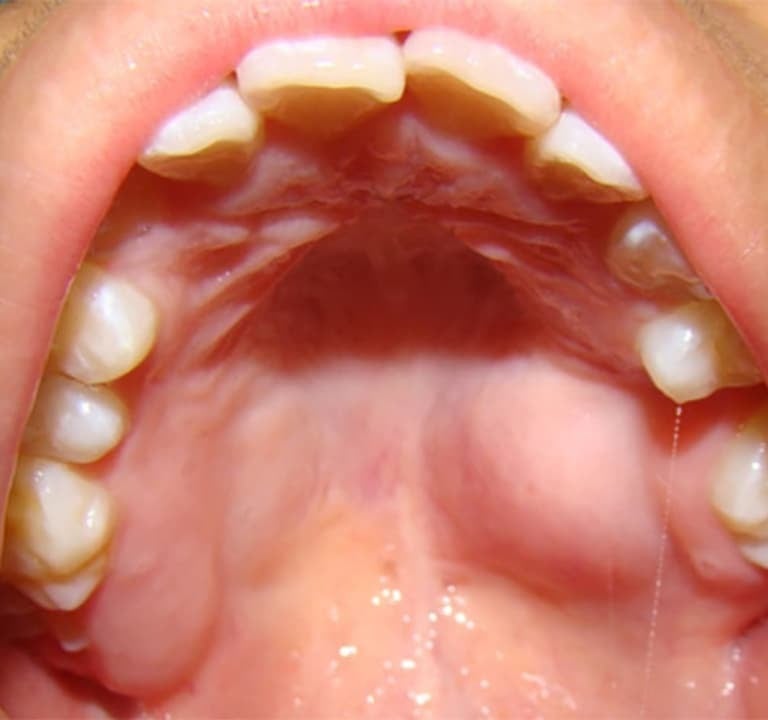

¿Has notado que tu paladar está inflamado o te duele al comer? Aunque muchas veces es un problema leve, en algunos casos puede indicar una infección o enfermedad bucal que necesita atención profesional. En Clínica Dental ADES, en Badajoz, te ayudamos a identificar la causa y a tratar el problema con las mejores soluciones.

El paladar inflamado puede tener varias causas, desde irritaciones leves hasta infecciones más serias. Algunas de las más comunes incluyen:

¿Cuándo Deberías Preocuparte por un Paladar Inflamado?

⚠️ Si la inflamación dura más de 10 días.

⚠️ Si tienes fiebre o ganglios inflamados.

⚠️ Si aparecen llagas o heridas que no cicatrizan.

⚠️ Si sientes dolor intenso al comer o beber.